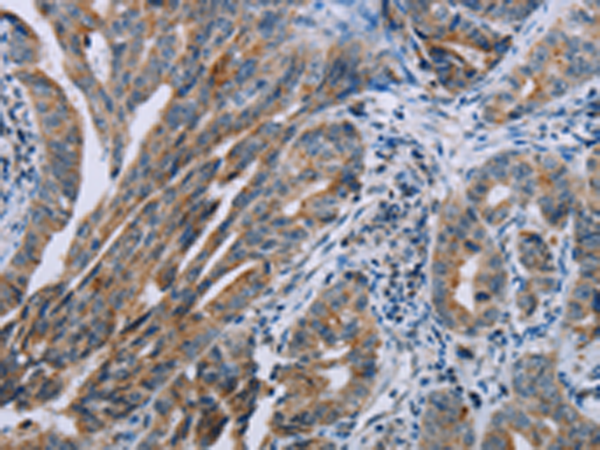

分类: 科研抗体货号: P05214别名: RNPC1; SEB4B; SEB4D; HSRNASEB; dJ800J21.2应用: WB,IHC反应种属: Human, Mouse